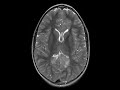

Neurofibromatosis Type 1

In this patient with a history of neurofibromatosis type I (NF1), there are numerous scattered foci of T2 FLAIR hyperintensity involving the subcortical white matter, corpus callosum, basal ganglia, and medial cerebellar hemispheres, many of which demonstrate mild enhancement. There is expansile T2 FLAIR hyperintensity involving the genu and splenium of the corpus callosum where there are areas of restricted diffusion. Findings are most compatible with multifocal gliomas and myelin vacuolization which are typically seen in preteen NF1 patients as was this patient.